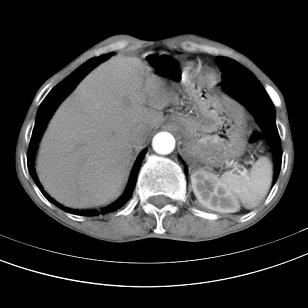

标题: 男,65岁,反复右上腹痛, [打印本页]

标题: 男,65岁,反复右上腹痛,

胃镜提示十二指肠占位